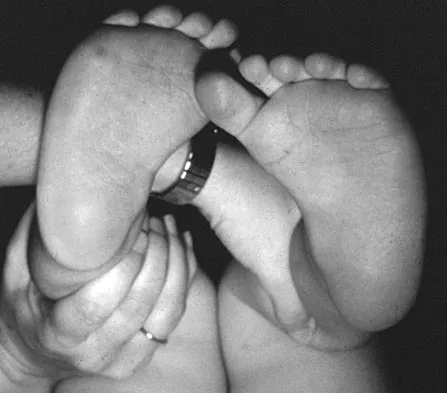

Figure 16 shows the clinical photograph of a 3-month-old infant with a foot deformity that has been nonprogressive since birth. Examination reveals that the deformity corrects actively and with passive manipulation. There is no associated equinus. Management should consist of

Explanation

The patient has bilateral metatarsus adductus deformities. In a long-term follow-up study by Farsetti and associates, deformities that were passively correctable spontaneously resolved and no treatment was required. More rigid deformities were successfully treated with serial manipulation, with good results in 90%. There were no poor results. Therefore, observation is the management of choice for passively correctable deformities. In feet that are more rigid, serial manipulation and casting is the management of choice.